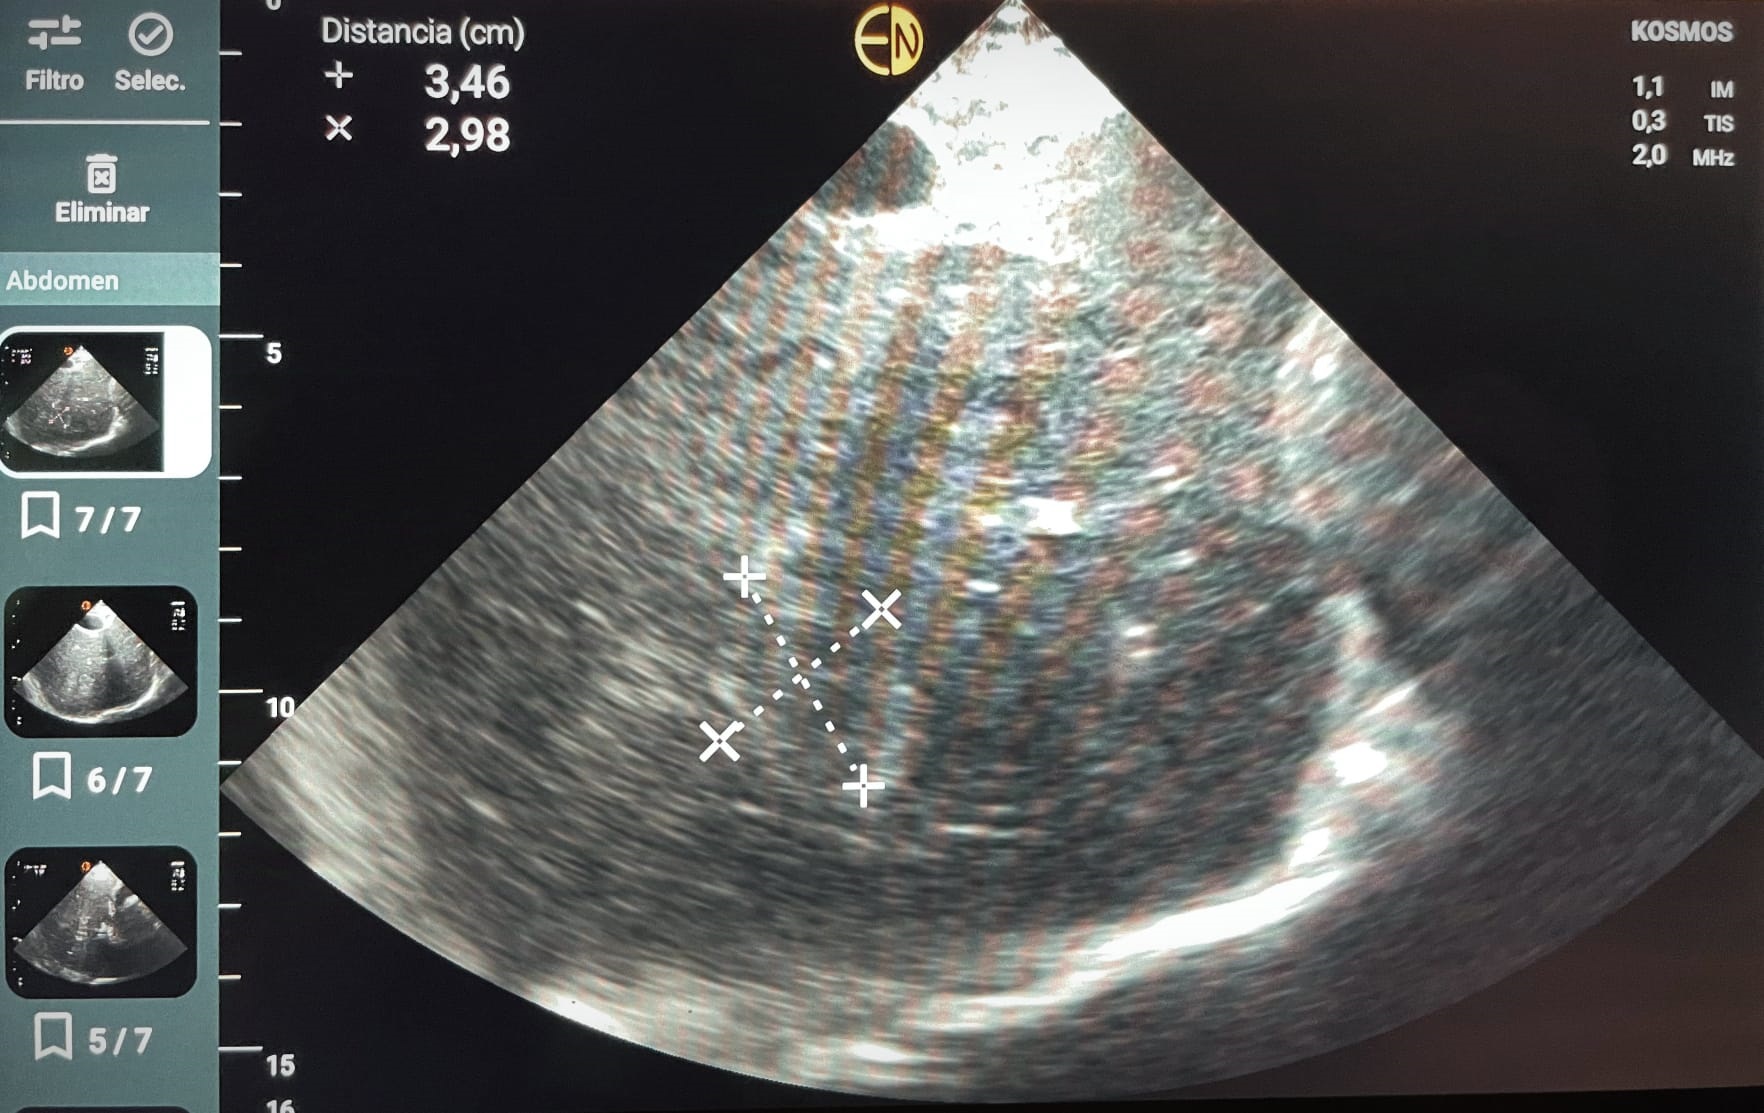

Ecografía POCUS abdomen: se identifican al menos dos imágenes hiperecogénicas en parenquima hepático, con regiones de aspecto algo heterogéneo, la mayor de ellas de 4,9 cm diámetro máx. No líquido libre. Vesícula distendida, sin signos de colecistitis o dilat vía biliar.